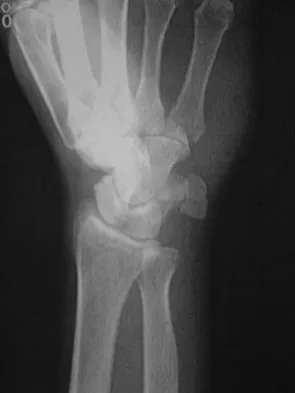

A 19-year-old woman fell onto her nondominant hand 6 weeks ago. Radiographs are shown in Figures 37a and 37b. A decision has been made to treat this fracture surgically. What is the best approach to treat this fracture?

Explanation

Displaced fractures of the scaphoid are best treated with compression screw fixation. Proximal third fractures (as in this patient) are optimally approached via a dorsal approach to ensure proper reduction and compression. Fractures of the scaphoid waist can be approached either by a volar or a dorsal approach. Kirschner wire fixation is limited to proximal pole fractures that are too small to accommodate the trailing head of a compression screw. Retting ME, Raskin KB: Retrograde compression screw fixation of acute proximal pole fractures. J Hand Surg Am 1999;24:1206-1210.